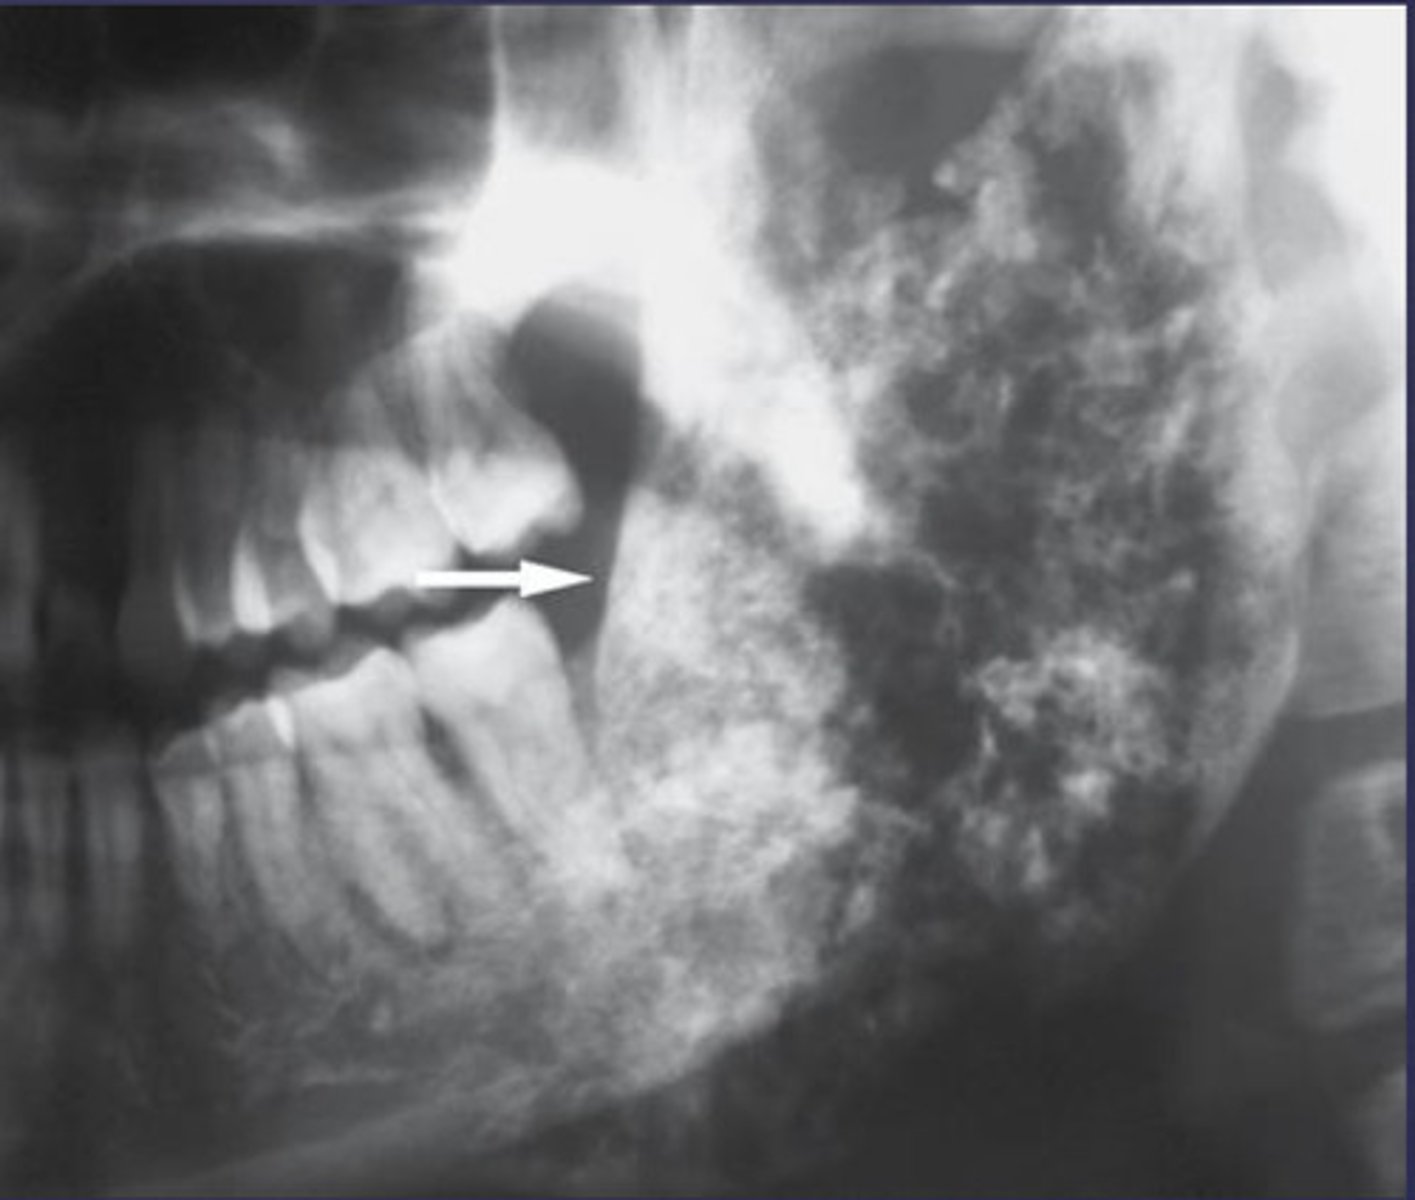

Patient's radiograph shows the following. What is the diagnosis?

- Garrington sign (widened PDL space)

- Ragged, ill-defined radiolucent/paque mixed area

- 'sun ray' periosteal reaction

- spiked root resorption pattern

osteosarcoma